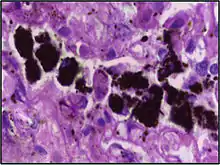

Comparison of pigmented pulmonary macrophages

| Disease | Macrophage name | Macrophage pigment appearance (HE stain) | Usual macrophage location | Associated medical history | Image | Image comment |

|---|---|---|---|---|---|---|

| Anthracosis | Black-brown granules | Interstitium (perivascular) |  |

Black arrow shows interstitial anthracotic pigment. Nearby macrophages (white arrow) can be presumed to contain anthracotic pigment. | ||

| Respiratory bronchiolitis | "Smoker’s macrophages" | Yellow to light brown and finely granular[4] | Airways (especially respiratory bronchioles) | Tobacco smoking |  |

Smoker's macrophage in center |

| Chronic pulmonary congestion | Siderophages | Brown-golden and refractile.[5] | Alveoli[6] |

|

|

Siderophage (black arrow), and interstitium with edema, hemosiderin deposition (black arrow) and collagenous thickening, indicating heart failure. |